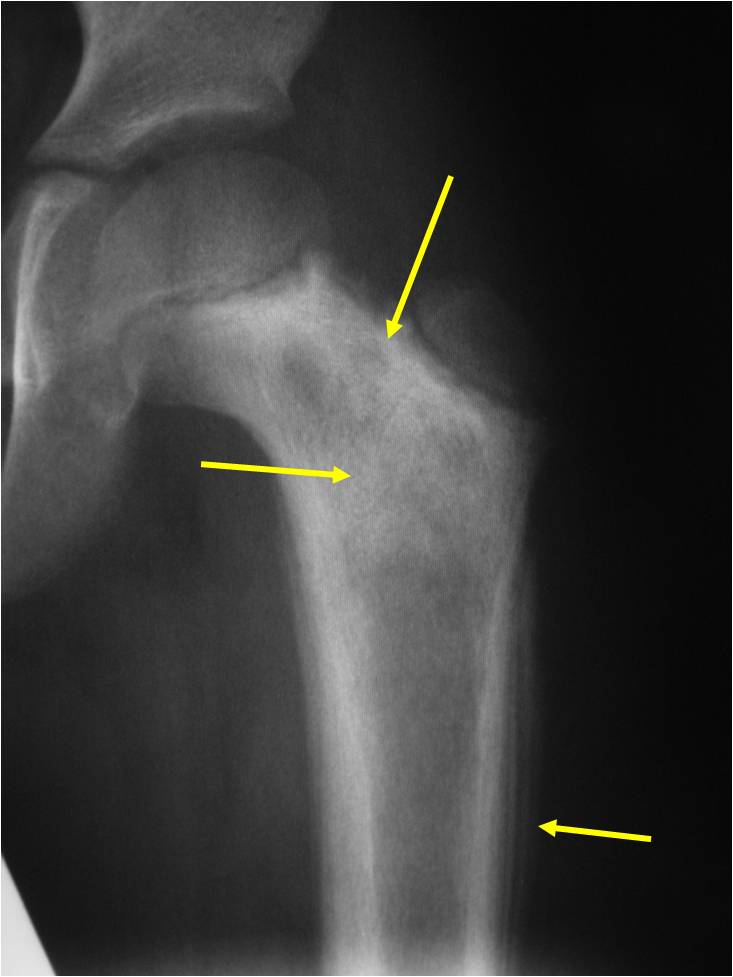

Radiographic Presentation

- Permeative or moth eaten bone destruction

- Ill defined and malignant appearing

- Bony changes are often subtle

- Soft Tissue Mass in 90% of of cases

- Periosteal Reaction in 50% of cases

- Onion Skin (colic pattern of irritation)

- Hair on End (rapid continuous lifting of periosteum)

- Reactive Bone Sclerosis is rare but occurs in 10% of cases

- No cartilage or bone production by tumor

- Pathologic fracture in 10-15%

- Ewing sarcoma rarely presents as a geographic, benign appearing tumor similar to a cyst or eosinophilic granuloma